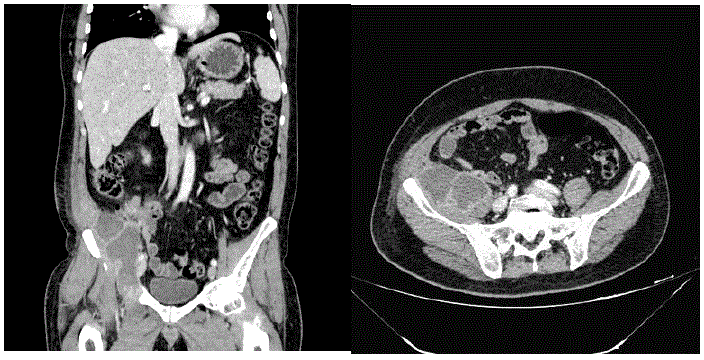

Realizada tomografia de abdome (imagens a seguir):